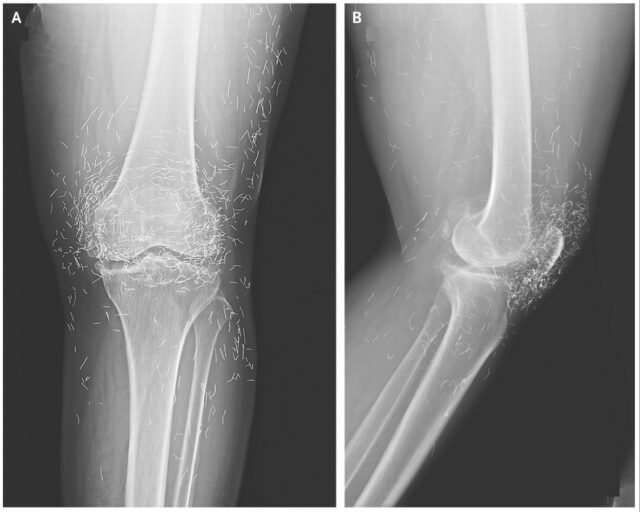

Ele foi ao hospital mais tarde porque os joelhos eram muito dolorosos. raios X O joelho esquerdo revelou que o brilho no interior do pulso estava espessado e solidificado. Também houve crescimentos ósseos, chamados Spurs, nas partes internas do osso do sébio e da articulação do joelho.

Os médicos também viram centenas de manchas de raios X ao redor da articulação do joelho, que provaram ser pequenos fios de ouro.

Diagnóstico: Os médicos descobriram que os fios foram inseridos como parte dos tratamentos de acupuntura das mulheres. Esses fios de ouro curtos e estéreis eram intencionalmente deixado no tecido Para garantir a estimulação contínua.

Em seu relatório sobre o estojo do joelho, os médicos notaram que os fios de ouro inseridos durante a acupuntura poderiam ser desafiados a ler raios-X.